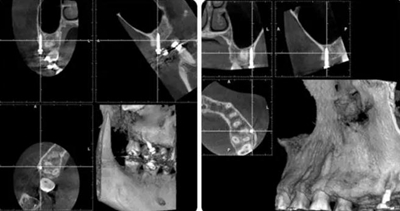

治療8個月,換0.018*0.025"CuNiTi弓絲,植入支抗釘,植入位點為上頜第一磨牙根上方顴牙槽嵴處,使其與牙根平行。同時嘗試性牽引遠移上牙列。

(3)全牙列遠移種植釘植入位點為上頜第一磨牙根上方顴牙槽嵴處,使其與牙根平行,在術(shù)前需CBCT確認骨量,否則有脫落或無法植入的可能。